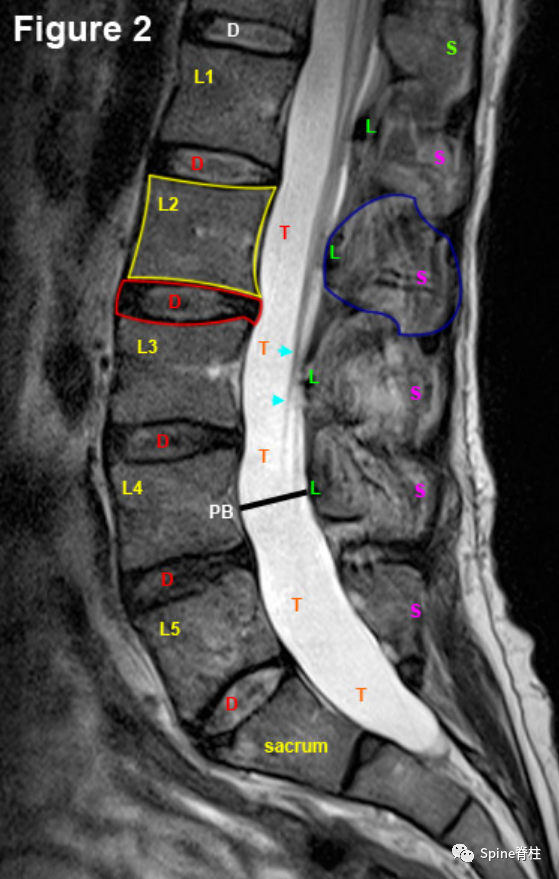

腰椎MRI正中矢状面(mid-Sagittal Region)。可见两种主要的骨结构:方形椎体(黄色轮廓)和后弓的棘突(蓝色轮廓和S)。棘突与椎板的连接构成后弓的前边界,后弓也形成中央椎管的后部。这被黄韧带覆盖(绿色L)。椎体和后弓之间的极度高信号空间(几乎纯白色)是硬膜囊(红色T),充满着脑脊液。黑线为椎体后部(PB)、椎弓根和椎板之间的距离,为椎管的直径。在正中矢状面中,马尾神经根通常不太明显(淡蓝色箭头),除非它们靠近神经孔(未显示)。位于5个腰椎椎体之间的是5个腰椎间盘(红色轮廓和D),它们承载身体80%的轴向载荷。